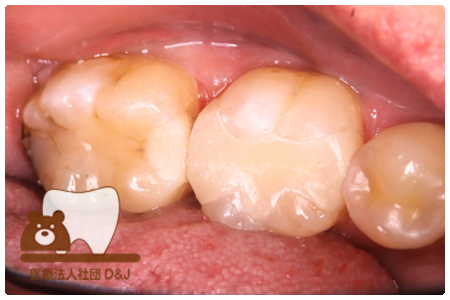

症例7フルジルコニアクラウン

治療前

治療後

43歳 女性

- 治療内容

- 虫歯で大きく失われた歯に対して、土台としてファイバーコアを使用し、その上にフルジルコニア製の被せ物を装着しました。見た目と強度を両立した自由診療の治療です。

- 治療期間

- 5カ月

- 費用

- 自費

フルジルコニアクラウン:77,000円(税込)(R7.12月現在)

- その他の治療の費用は含まれておりません。

- リスク・副作用

- 硬い素材のため、かみ合う歯に負担がかかることがあります。将来取り外す場合に歯に負担がかかることがあります。強い力が加わると、まれに欠けたり割れたりすることがあります。